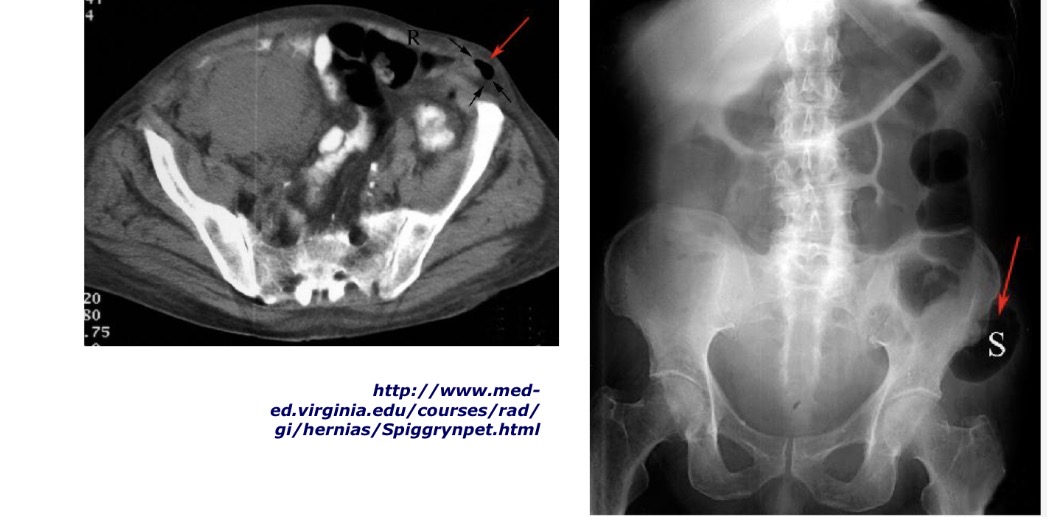

Pusmėnulinės linijos, linea semilunaris (Spigelius), išvaržų radiografiniai vaizdai